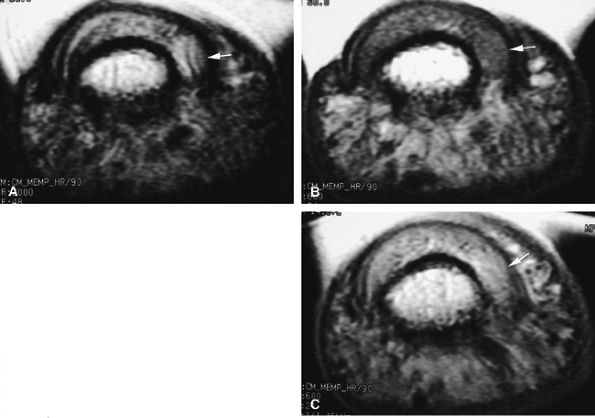

FIGURE 11.13 ● Proximal tear of the radial collateral ligament (RCL) of the third metacarpophalangeal joint. Comparison of axial STIR (A) and post-contrast fat-suppressed T1-weighted image (B). Focal irregularity and slight hyperintensity of the RCL can be seen on the STIR image. Strong enhancement of the proximal part of the RCL and bone edema (asterisk) is seen on the T1-weighted images. MC, metacarpal.